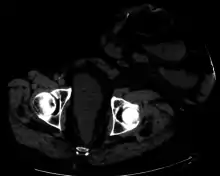

Parastomal hernia is the most common late complication of stomata through the abdominal wall, occurring in 10 to 25% of the patients.[1]

One well-known form of an artificial stoma is a colostomy, which is a surgically created opening in the large intestine that allows the removal of feces out of the body, bypassing the rectum, to drain into a pouch or other collection device. This surgical procedure is invoked usually as a result of and solution to disease in the GIT. The procedure involves bisecting this tube, usually between the later stage of the small intestine (ileum) and the large intestine or colon, hence colostomy, and exiting it from the body in the abdominal region. The point of exiting is what is known as the stoma.

For greatest success and to minimize negative effects, it is preferable to perform this procedure as low down in the tract as possible, as this allows the maximal amount of natural digestion to occur before eliminating fecal matter from the body. The stoma is usually covered with a removable pouching system (adhesive or mechanical) that collects and contains the output for later disposal. Modern pouching systems enable most individuals to resume normal activities and lifestyles after surgery, often with no outward physical evidence of the stoma or its pouching system.